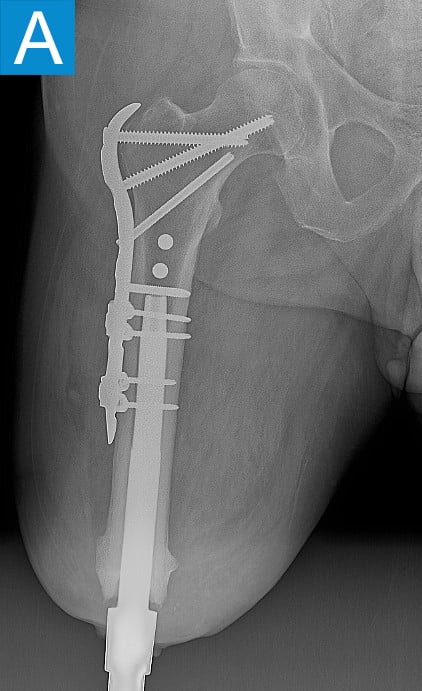

Standing radiographs showed periosteal reaction to the distal femoral isthmus, and given the chronicity of his infections the decision was made to stage the transfemoral amputation and osseointegration implant insertion (Figure 1b). During the amputation, the tibial and peroneal nerves underwent targeted muscle reinnervation to the motor branches of the medial and lateral hamstrings, respectively. Cement mixed with tobramycin and vancomycin was placed in the femoral canal, and the remaining musculature was purse stringed around the residual femur. His proximal cultures were negative, and so no further antibiotic treatment was given. Approximately 8 weeks later, the antibiotic spacer was removed and a press fit femoral osseointegration implant was placed in a percutaneous procedure (Figure 2a). Cultures of the canal remained negative.

Figure 1. Preoperative X-rays show (A) static cement spacer on antibiotic suppression and (B) an antibiotic cement spacer in the residual femur.

He started progressively loading the implant at 2 weeks and received his full prosthetic leg with simple hinged knee at 6 weeks. At 3 months he no longer used assist devices and at 3.5 months his prosthesis was changed to a microprocessor-controlled knee. Shortly after receiving the new knee, he stumbled stepping over a ledge and fell, sustaining a subtrochanteric proximal femur fracture (Figure 2b). The fracture extended to the tip of the implant, which remained stable in the bone. He underwent open reduction and internal fixation of the femur fracture with a proximal locking plate (Figure 2c). He did not wear the prosthetic leg for 10 weeks, when he began gradually loading the femur. He resumed full weightbearing without assistive devices about 6 weeks later.

Figure 2. Postoperative X-rays shows (A) a femoral osseointegration implant; (B) a subtrochanteric proximal fracture; (C) the femur fracture repaired by open reduction and internal fixation with a proximal locking plate.